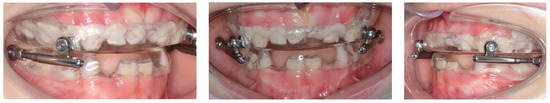

5. Results